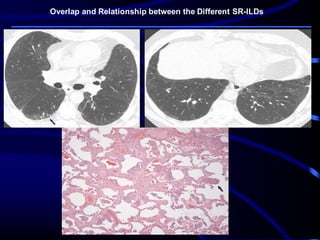

Overlap and Relationship between the Different SR-ILDs

The clinical, radiologic, and histologic features overlap among the different SR-

ILDs. The overlap is most significant between RB-ILD and DIP. They may be

different components of the same histopathologic disease spectrum, representing

diverse degrees of severity of the same process caused by chronic smoking.

Respiratory bronchiolitis or DIP changes at histologic analysis are very common

in patients with PLCH, correlating with the cumulative exposure to cigarette

smoke, and are often accompanied by significant ground-glass attenuation at

high-resolution CT .

Smokers who develop IPF often have RB-ILD and DIP changes at high-resolution

CT and histopathologic analysis , and patients with DIP may develop a high-

resolution CT pattern of fibrotic NSIP over time .

A combination of SR-ILD–related high-resolution CT findings, such as ground-

glass opacities, cysts, micronodules, septal thickening, and honeycombing, can

be seen in the same patient, confounding radiologic classification into a discrete

smoking-related entity.